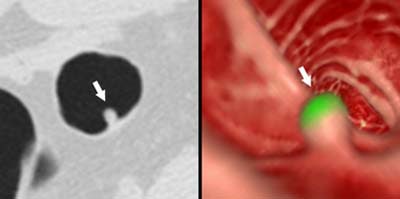

![]() |

| Left to right: prone and supine axial images of a flat tubular adenoma along the fold of the hepatic flexure. The lesion was missed by both radiologists, but detected by CAD (represented by lines in image at left). From Fletcher JG, Summers RM, Johnson CD, MacCarty RL, Wilson LA. Lessons in Detection: Contribution of Computer-aided Detection with Perceptively Challenging Lesions at CT Colonography. Supplement to Radiology November 2002, Vol. 225, p. 304. RSNA December 1-6, 2002, Chicago. Image courtesy of Dr. Joel Fletcher, © Mayo Medical Foundation, 2002. |